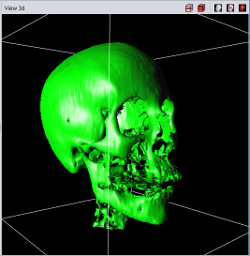

|

|

|

| Point Cloud | Marching Cube | Texture |

Currently four different segment visualization methods can be choosen.

The 3D segment visualization methods can be set for each individual segment. This can be done in the "view 3d" tool pane.